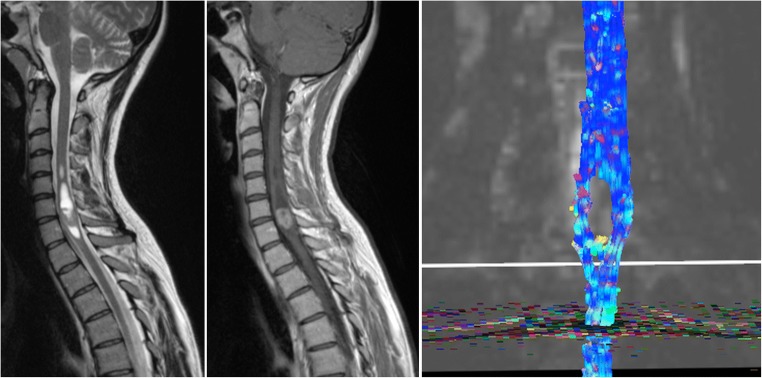

DTI and tractography reconstruction can be helpful for surgical planning in patients with brain or spinal cord masses. It shows white matter tracts as well as displacement or interruption of these tracts secondary to different pathologies. Slow-growing tumours displace the fibres surrounding the lesion, whereas in ischaemia or trauma, representing more acute insults, the fibres are usually interrupted [45] (Fig. 6).

Fig. 6.

DTI for surgical planning. Patient with an ependymoma in the lower cervical spinal cord with areas of high T2 signal (a) and enhancement after gadolinium administration (b). DTI shows displacement of the fibres (c), which is usually consistent with a slow-growing lesion